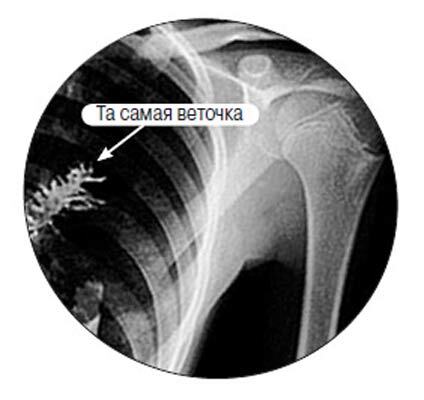

- Операція розпочиналася зазвичай. Спочатку ми розкрили грудну клітку, - згадує Надія Бокарева, лікар-онколог Республіканського клінічного онкологічного диспансеру, що брала участь в хірургічному втручанні. - Потім намацали щільне утворення. Коли зробили надріз скальпелем, зрозуміли, що з легкого стирчить щось незвичайне, чужорідне. Стали розсікати далі - і остовпіли: здалися ялинкові голки, а потім і сама гілочка ялинки. Причому голочки були зелені, трохи з жовтим відтінком, але свіжі. Ялинка просто вросла в легеню. Ми не могли повірити своїм очам.

Частина легкого і бронха разом з ялинкою довелося, звичайно, видалити. Натомість жодних онкологічних новоутворень не знайшлося. Операція, яка тривала близько двох годин, завершилася успішно ".